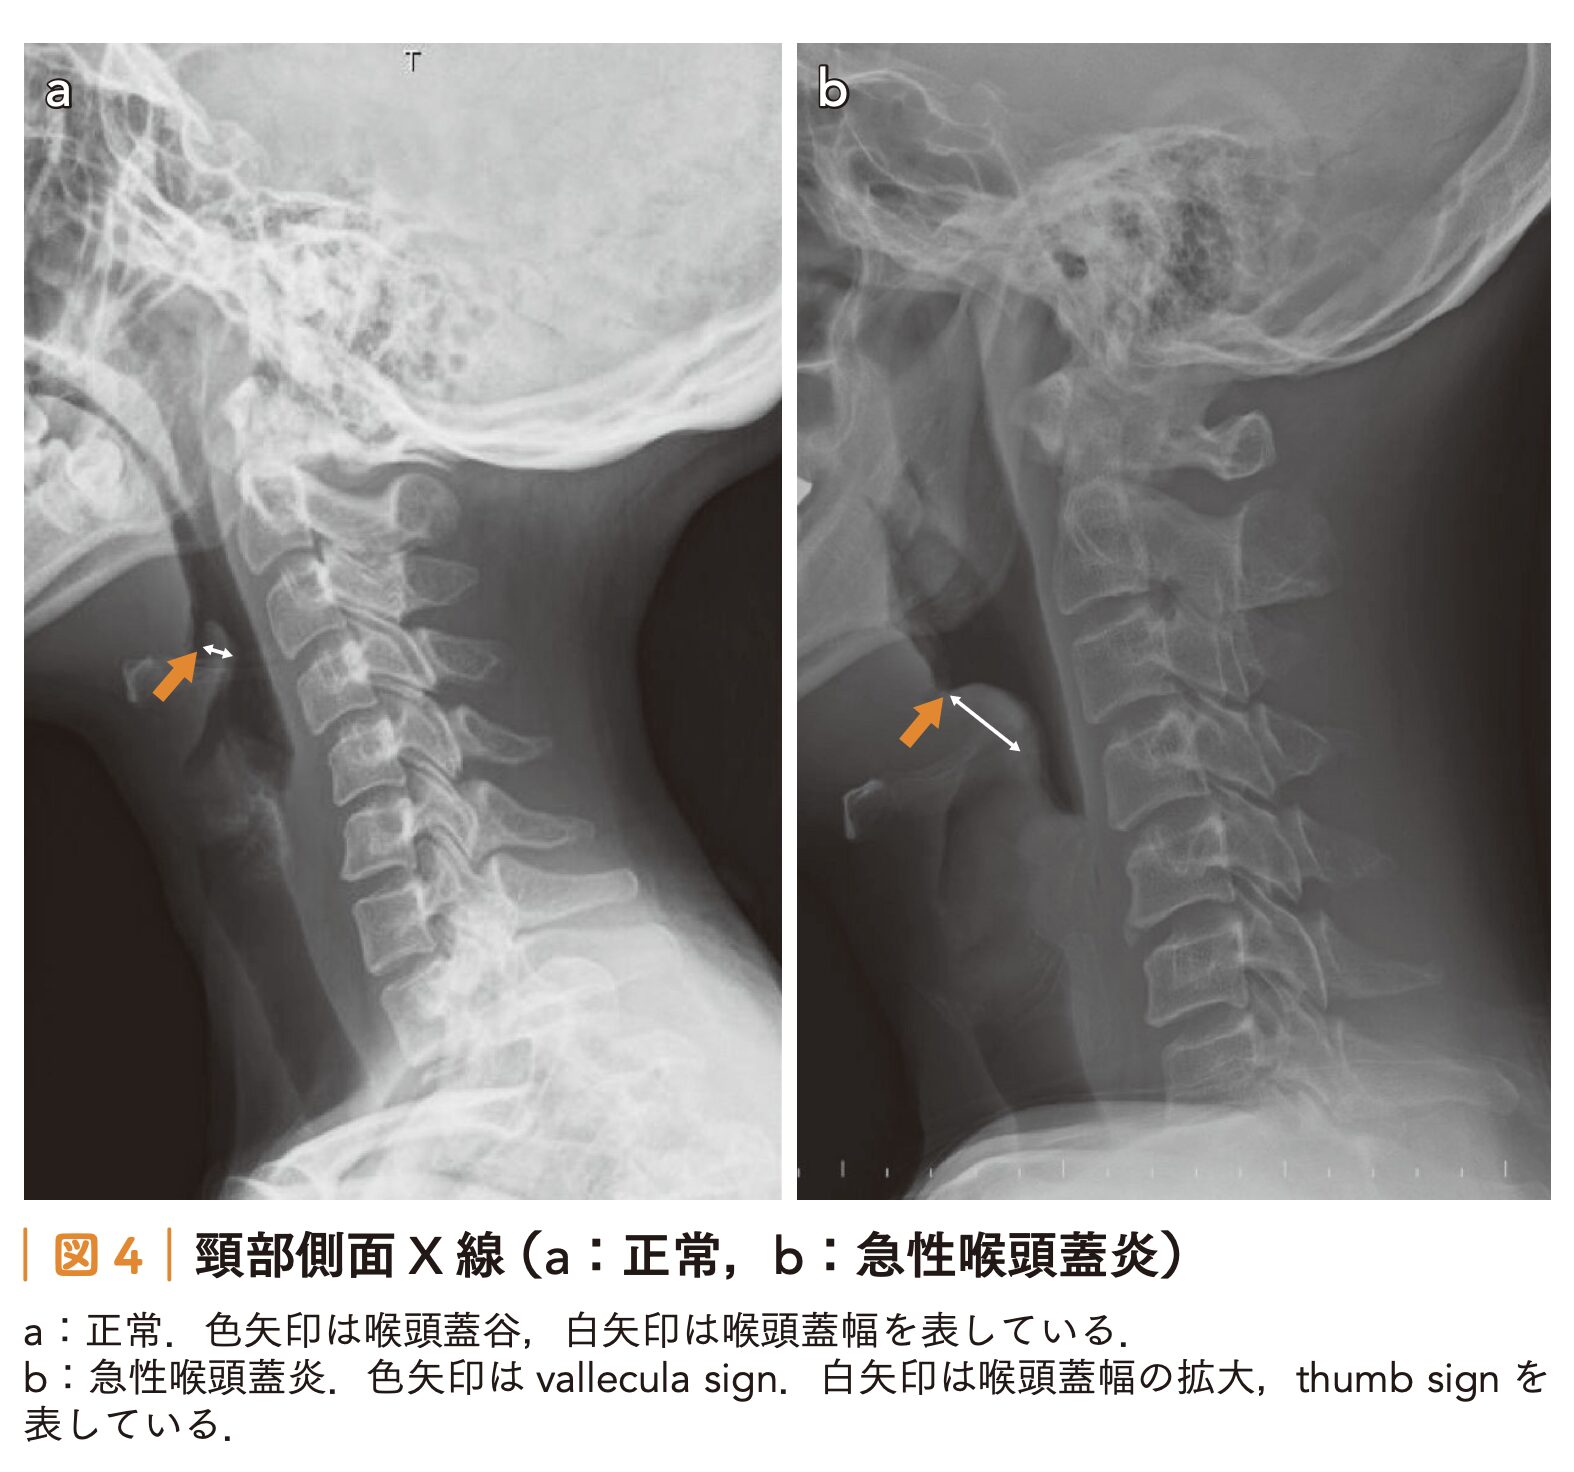

頸部側面X線撮影

- 急性喉頭蓋炎を疑う際の頸部側面X線撮影における各所見の感度と特異度は以下の通りです。

- thumb sign(広く丸い喉頭蓋):感度 65.9~66.7%、特異度 94.0~100%

- vallecula sign(喉頭蓋谷の消失):感度 53.9~71.4%、特異度 88.1~100%

- 喉頭蓋幅>6.3 mm:感度 75.8%、特異度 97.8%

- これらのX線画像所見は、急性喉頭蓋炎の診断において基本となる喉頭ファイバー検査(喉頭蓋の腫脹や発赤の直接確認)の実施が困難な場合に有用とされています。